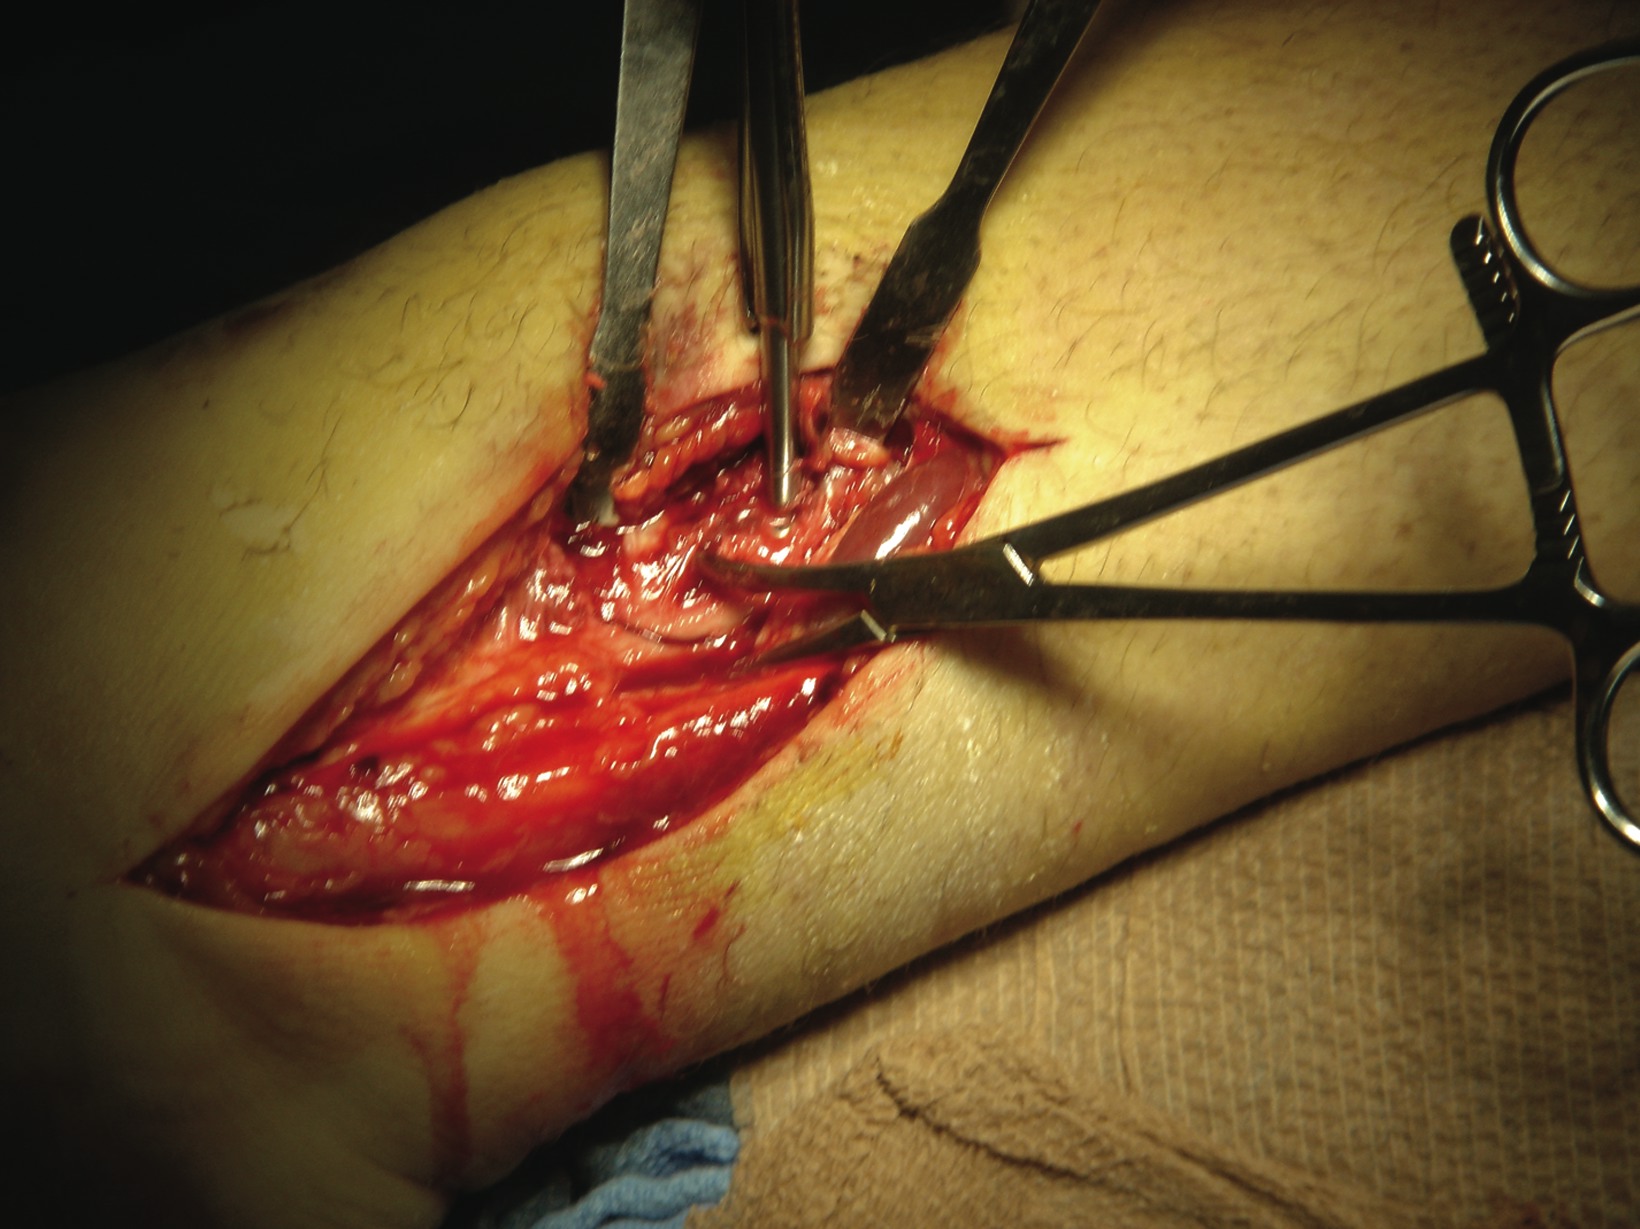

All athletes, regardless of the level of performance, will need the appropriate physical therapy modalities and rehabilitative techniques to complete functional recovery from an ankle fracture. Athletes who are at the competitive amateur level or professional level will need to return to their performance level sooner than the weekend warrior. Athletes whose career is based on their performance and return to competition will need complete rehabilitation. These individuals have no financial constraints as compared to some amateur athletes and recreational athletes. There are three phases of rehabilitation: the acute phase, the recovery phase and the functional phase. Phase one is the reduction of pain, inflammation and edema while retarding muscle atrophy of the lower extremity complex. Improving range of motion is also a major component in this acute phase. Phase two involves improving range of motion, improving lower extremity strength, increasing neuromuscular control and regaining normal arthrokinematics (defined as function of the joint) in single planes and triplanar motion of the ankle. Phase three involves increasing power of the lower extremity complex, increasing neuromuscular control in multiple planes of motion and utilizing sport-specific training for a full return to sport.30,31 A consideration with treating athletes is that if the athlete is inactive after his or her injury, the athlete loses training adaptation. This means the athlete will “detrain” as the individual’s physiological function reverts to the normal untrained state.32 It is most essential that the athlete remain active in some form of alternative exercise or maintenance program during the rehabilitative period in order to maintain his or her mental and physical strength. Alternative activities include water running and weight training of the upper extremity and the noninvolved lower extremity. Any form of maintaining aerobic capacity, neuromuscular coordination and muscle strength will help reduce injury.30 When it comes to ankle fractures in competitive athletes who require full function of their joints and motion, these individuals will need complete reduction with no malalignment. In previous studies, authors have shown that 1 to 2 mm of displacement of the fibula can cause an increase in tibiotalar contact up to 42 percent. This can lead to increased arthrosis and pain, which can reduce the longevity of playing careers.33 The trend is to perform open reduction and internal fixation of the fracture for early mobilization/rehabilitation, especially when it comes to early season injuries and reducing recovery time in order to facilitate a return to mid-season or end of the season play.7 If an injury occurs at the end of the season, the goal is getting an athlete fully rehabilitated for offseason training. If the podiatrist manages the athlete surgically with open reduction and internal fixation, one may have the patient begin early partial weightbearing in a walking boot with passive range of motion exercises at one to two weeks postoperatively. If you are treating professional athletes or high level college athletes, one may utilize bone stimulation in the postoperative management regimen to increase healing time. The athlete can begin physical therapy at two weeks postoperatively with phase one of rehabilitation exercises. The first phase of rehabilitation will include passive range of motion exercises and cryotherapy, which clinicians can initiate immediately after surgery by having the patient wear circulating cryotherapy boots at the hospital or surgery center. After the patient has met the goals of the first phase of rehabilitation, one may proceed to the second phase, which is usually initiated at three to four weeks postoperatively. One must remember to use pain as a guide in dealing with any type of rehabilitation procedure. In the second phase, patients may initiate strengthening with Theraband, range of motion exercises and proprioception exercises with a biomechanical ankle platform system (BAPS). Advise these patients that when they use theraband, they should use the least resistant bands initially. Toward the end of the second phase, the athlete should begin using a wobble board to improve proprioception and begin closed kinetic chain activities such as walking and loading. In the sixth to eighth week post-op, the athlete should begin the third phase of rehabilitation, which involves improving power, increasing neuromuscular control and utilizing sport-specific training of the lower extremity for a full return to sport.31 In the functional phase of rehabilitation, one may initiate plyometric (defined as “used to restore force”) exercises such as double-leg jumping, single leg jumping, four-square hopping, use of a minitramp and running to cutting progressions.30,31 The athlete should continue neuromuscular exercises and leg control exercises in this phase as well. The hip and leg control exercises involve hip and knee strengthening, one-legged stance and agility drills. Sport-specific exercises involving jumping, cutting and kicking offer a final component to the rehabilitation process.31 In regard to the various physical therapy modalities, such as iontophoresis, ultrasound, contrast bathing and interferential stimulation, one should continue utilizing these modalities to reduce swelling, pain and improve motion. Protecting the injured extremity will be very important in the later stages of rehabilitation with taping and bracing. When the athlete returns to full speed activity, he or she should continue to utilize a supportive device indefinitely.

There are some controversies in regard to the postoperative management of ankle fractures. One controversy is whether to begin early partial weightbearing versus non-weightbearing. The standard postoperative management advised by the Association for the Study of Internal Fixation after the internal fixation of ankle fractures is the use of crutches without weightbearing. The majority of literature supports early range of motion and protected weightbearing after anatomical reduction with stable internal fixation. In previous prospective randomized studies on early weightbearing and mobilization of surgically stabilized ankle fractures, Ahl, et. al., found that early active ankle movements with the addition of weightbearing improve rehabilitation following the surgical repair of ankle fractures.25-29 His series of studies also showed an improvement in ankle dorsiflexion and plantarflexion of the operated ankle at three and six months postoperatively with early mobilization and weightbearing. Other benefits of early weightbearing and mobilization include a reduction of stiffness, swelling, muscle atrophy and disuse osteopenia. Once you have decided how to treat the patient, then you can decide when to begin rehabilitation.